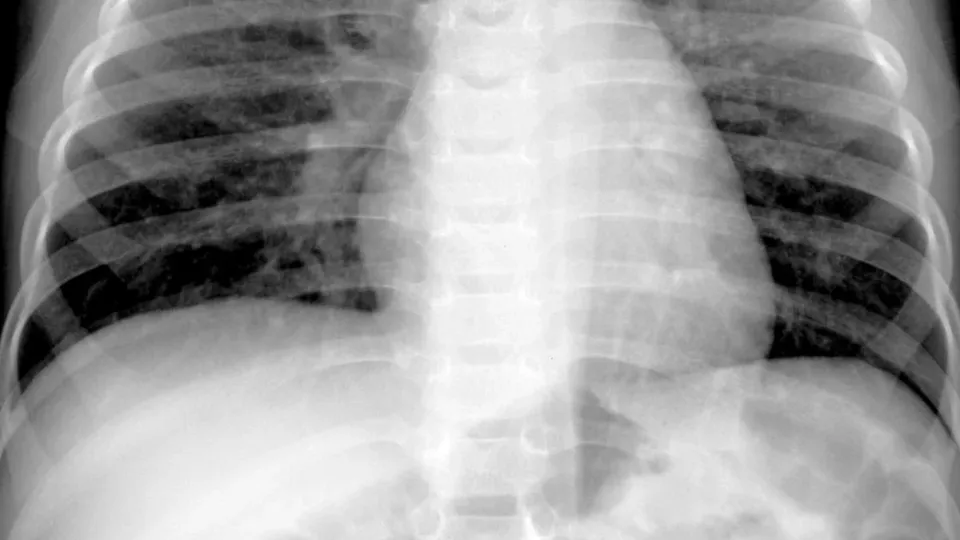

O HMPV, que foi identificado pela primeira vez em 2001, é um vírus que circula sazonalmente e é responsável por infecções respiratórias, especialmente em crianças e idosos. Embora os sintomas possam variar de leves a moderados, como tosse, febre e congestão nasal, em casos mais graves, pode levar a complicações como bronquite e pneumonia.

Os médicos alertam que, apesar do aumento nos casos, a maioria das infecções por HMPV é leve e muitas vezes não é diagnosticada, pois os sintomas são semelhantes aos de outras doenças respiratórias. “As características clínicas são muito difíceis de distinguir de outras doenças virais, e não testamos rotineiramente para o HMPV como fazemos para Covid, gripe ou VSR”, comenta Leigh Howard, professora associada de doenças infecciosas pediátricas.